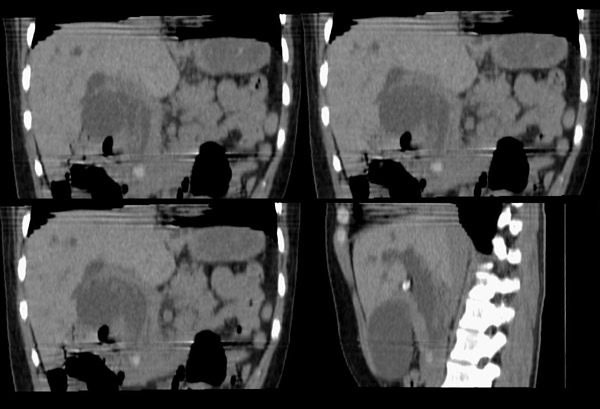

胆总管矢状及冠状重建:

胆总管结石\\肝左叶肝内胆管结石,胆道蛔虫钙化伴胆系梗阻\\胆囊积水.

整个胆道系统内可见多发蛔虫钙化改变,胆道扩张.

行胆囊切除术及胆总管探查术:探查见肝脏大小正常,肝缘稍钝,肝表面光整,胆囊大小12*3*3cm3,壁水肿增厚约0。5cm,张力稍高,胆囊与大网膜呈纤维粘连;胆总管宽约2cm,壁明显增厚,触摸胆总管,隐约可触及一条状物,于胆总管做一长约1、5cm的纵行切口,用取石钳在胆总管内取出一条长约16cm长黑色的长条状物,较脆易折断,宽约0、6cm,证实为蛔虫尸体。用探子往下探,未发现下端结石最后诊断:胆道蛔虫症继发胆系梗阻性扩张。